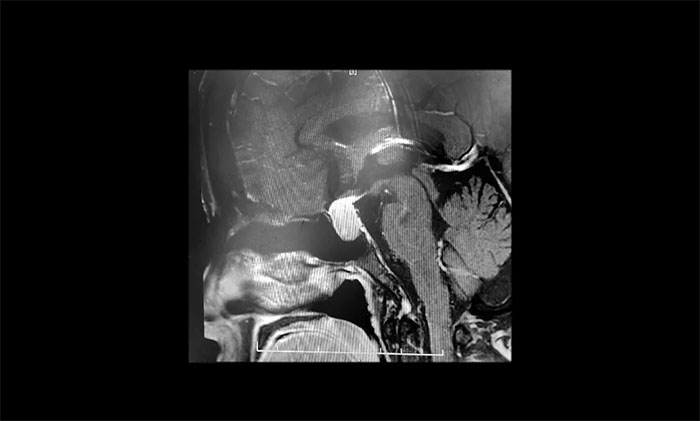

聽到腦袋里長了腫瘤,張阿姨一家人非常緊張,為謹(jǐn)慎起見,張阿姨在家人陪同下,特地到上海專業(yè)腦科醫(yī)院求醫(yī)復(fù)診。經(jīng)鞍區(qū)MRI平掃+增強(qiáng)檢查顯示:蝶鞍顯著擴(kuò)大,鞍區(qū)見T1、T2中等信號(hào)實(shí)性腫塊樣占位病變,垂體柄明顯縮短,病變總矢橫高徑約1.2*1.6*1.8cm,病變突破鞍膈,向鞍上生長,推移視交叉,視交叉受壓、上抬。

▲ 垂體大腺瘤超蝶鞍生長